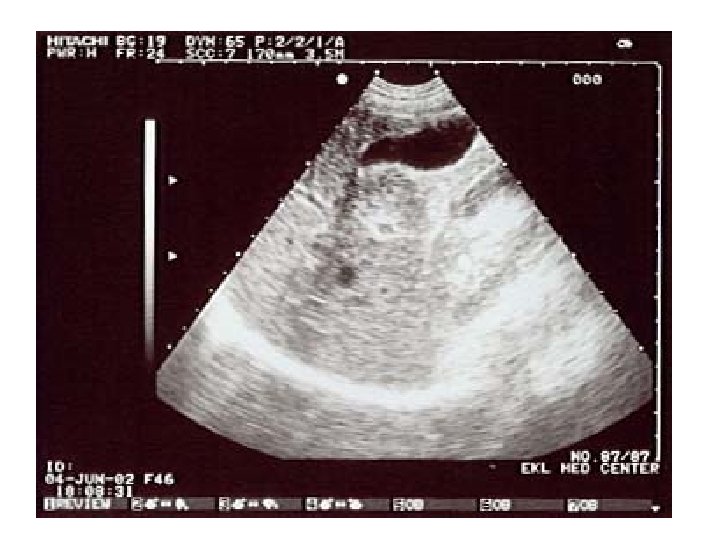

Ultrasound imaging: carotid artery • This is also a carotid artery. • The flow is not all in the same direction. It is turbulent, like rapids in a river. • This is usually due to a build-up of fatty deposits in the artery